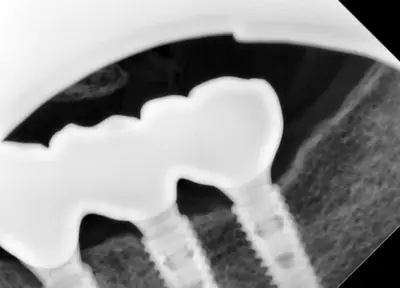

치과 치료를 두려워하는 분들을 위해, 진정요법을 활용한 사례를 소개합니다. 부산에 거주하던 60대 여성 환자가 치아가 많이 손상되어 임플란트와 브릿지 치료를 받았는데, 병원 트라우마와 공포로 어려움이 있었어요. 의식하 진정요법을 통해 깊은 낮잠 같은 상태에서 안전하게 치료를 받았고, 수술 과정도 성공적이었어요. 이 방법은 전신마취보다 안전하고, 환자도 큰 두려움 없이 치료를 마칠 수 있어요. 치과 공포증이 심한 분들도 전문가와 상담 후 진정요법을 고려해보시면 좋겠습니다.